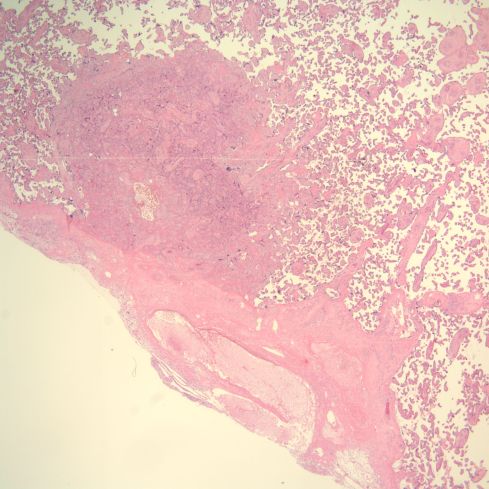

A perhaps understudied aspect of the spiral arteries in the basal decidua is their appearance when they underlie lesions of placental infarction, retroplacental hematoma, subchorionic thrombohematoma, and infarction hematoma. Those underlying infarctions may be distended with blood and thrombus (Figs 19-24).

Fig 19: The large, blood filled convoluted spiral artery at the base of the placenta shows lamina of fibrin. The infant was liveborn at 26 weeks of gestation, but was severely growth restricted. The mother had type 1 diabetes and chronic hypertension. The placenta had multiple infarctions. (H&E, 2x)

Fig 20: This view of the same spiral artery shows is proximity to a recent placental infarction. The presence of a thrombus in the vessel suggests that the infarction may have been caused by this very superficial thrombus, but there is no obvious clue as to how it formed. (H&E, 2x)

Fig 21: Another basal spiral artery from the same patient as in Fig 19 showing fibrin lamina and underlying a very acute placental infarction. (H&E, 4x)

Fig 22: In another area of the above vessel the infarction involves the basal decidua (“necrosis”) as well the villi. Surrounding viable appearing decidua shows acute hemorrhage between the decidual cells. A gross retroplacental hematoma was not present. (H&E, 10x)